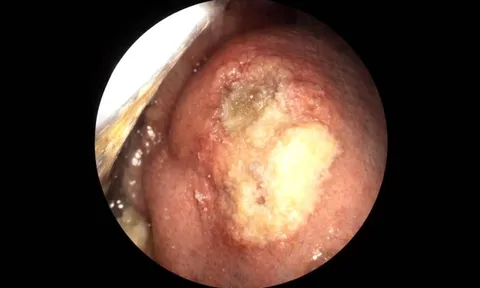

Mệt mỏi, sụt cân, người đàn ông đi khám phát hiện khối u gan 61mm

Sau 20 năm bỏ dở điều trị viêm gan và không tái khám, đến khi kiểm tra sức khỏe gần đây bệnh nhân mới phát hiện đồng thời nhiễm viêm gan C và xuất hiện khối u gan ác tính.